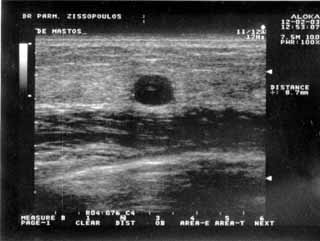

Ειμαι 34 χρονων εχω ενα κοριτσακι 2.5 χρονων και ενα αγορακι 6.5 μηνων το οποιο θηλαζω ακομη . Σημερα καθως θηλαζα πονουσα τη δεξια μου θηλη και μετα που τελειωσα ανακαλυψα ενα μικρο εξογκωμα στη θηλη, εσωτερικα. Ξερω οτι διαγνωση απο εδω δε μπορει να γινει, απλα ελπιζα να μου πειτε αν εκ πρωτης οψεως μπορει να οφειλεται στο θηλασμο? Μπορω να κανω μαστογραφια ενοσω θηλαζω η ενα υπερηχογραφημα θα ηταν καλυτερα και αν ναι παλι ανιχνευεται οτι και να ναι?